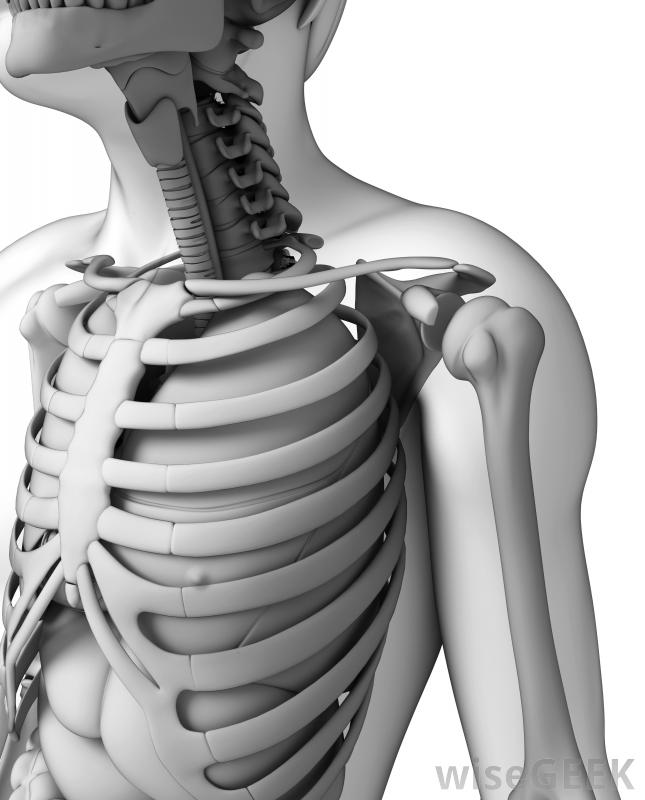

胸廓成形術是脊柱側凸患者的常見治療方法。

在脊柱側凸中,胸廓成形術可以減少肋骨隆起引起的外部畸形,這樣可以改善患者的整體外觀。此外,肋骨隆起可能會非常疼痛,因此移除它可能會減少或減輕與此相關的疼痛。例如,如果患者在倚靠椅背時感到不適,移除肋骨凸起有助于降低不適程度。

通常,醫生會與患者討論胸廓成形術的部位,因為肋骨會縮短以減輕疼痛緩解肋骨隆起,根據每個患者的情況進行分析和考慮。對于脊柱側凸的病例,肋骨的切除量取決于脊柱曲線和駝峰的嚴重程度和大小。